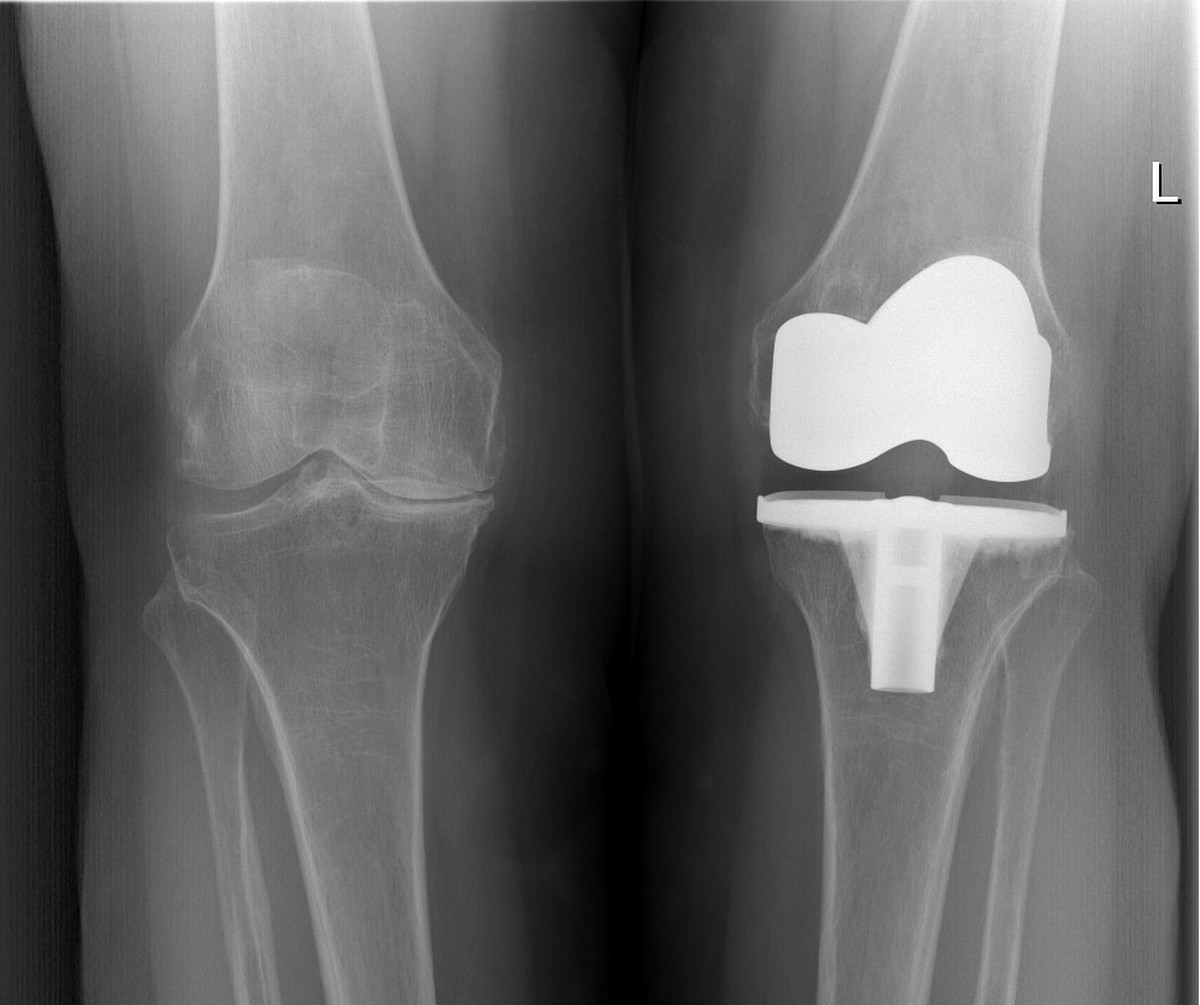

Jedan od najvećih problema s osteoartritisom je taj što se razvija postupno. Rani simptomi su često blagi i lako se pripisuju umoru ili ozljedi. Međutim, pravovremeno prepoznavanje simptoma i rana dijagnostika ključna je za usporavanje bolesti. Osim kliničkog pregled koji obavlja liječnik prva dijagnostička pretraga je RTG zahvaćenog zgloba koji ukazuje na stadij zahvaćenosti zgloba.

U težim slučajevima, kada druge metode ne pomažu, razmatra se operacija, poput ugradnje umjetnog zgloba.